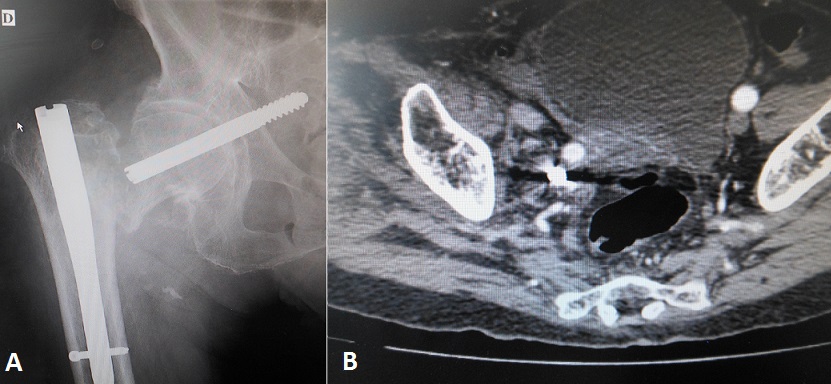

La plupart des fractures per et sous trochantériennes consolident après une ostéosynthèse par clou gamma. Néanmoins, dans certaines situations notamment chez les sujets âgées avec une qualité osseuse médiocre un démontage du matériel peut survenir. Celui-ci est suspecté devant une recrudescence de la douleur et l'impotence fonctionnelle totale du membre inférieur. La confirmation diagnostic se fait après radiographie standard qui montre chez notre patient une migration de la vis cervicale en intra pelvien. Malgré un examen vasculo nerveux normal, nous avons réalisé un angioscanner qui a montré le rapport intime de la vis cervicale avec les vaisseaux iliaques. Il faut toujours devant ce tableau éliminer un problème infectieux sous-jacent qui peut être la source du démontage. L'indication thérapeutique diffère en fonction de l'âge du patient. En effet, si chez le sujet jeune le but est d'obtenir une consolidation et d'éviter au maximum le recours à la prothèse totale de la hanche, chez le sujet âgé la déambulation et la marche rapide sont l'objectif principal afin d'éviter chez lui les complications de décubitus souvent mortels, ce qui justifie le recours à des PTH. Chez notre patient la difficulté était la proximité de la vis cervicale des vaisseaux iliaques, la présence d'un chirurgien vasculaire était nécessaire au moment de la reprise.